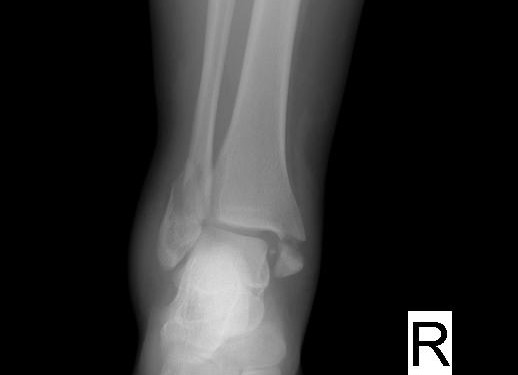

Maisonneuve kırığı:

Proksimal fibula kırığı ile birlikte iç malleol kırığı ya da deltoid bağ yaralanmasının birlikte görülmesidir. (Medial malleol kırığı + Distal tibofibuler ligamenlerin ayrışması + Proksimal fibula fraktürüdür.) ayak bileğinin pronasyona ve dış rotasyona zorlanması sonrası oluşur.

Maisonneuve kırığında ayak bileği travmalarında mutlaka proksimal fibulada bir patoloji olup olmadığına bakılmalıdır.

Tedavi: Ayak bileği stabilse uzun bacak ateli yapılır, Kırık unstabilse ligamenlerin tamiri cerrahi olarak yapılır.